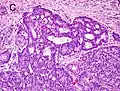

Cribriform pattern: Gleason grade 4

Gleason 4

Gleason pattern 4 glands are no longer single/separated glands like those seen in patterns 1-3. They look fused together, difficult to distinguish, with rare lumen formation vs Gleason 1-3 which usually all have open lumens (spaces) within the glands, or can be cribriform-(resembling the cribriform plate/similar to a sieve: an item with many perforations). Fused glands are chains, nests, or groups of glands that are no longer entirely separated by stroma-(connective tissue that normally separates individual glands in this case). Fused glands contain occasional stroma giving the appearance of "partial" separation of the glands. Due to this partial separation, fused glands sometimes have a scalloped (think looking at a slice of bread with bite taken out of it) appearance at their edges.[4][7]